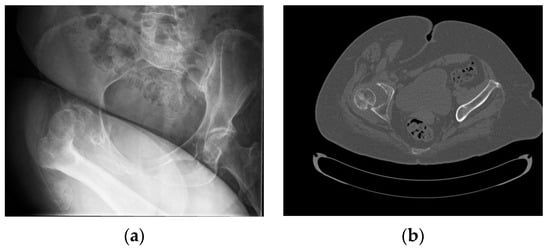

2. Case Presentation

2.1. Two-Stage Open Reduction

2.3. Case Follow-Up